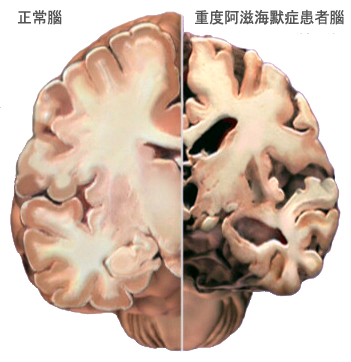

由于脑神经细胞的死亡与脑组织的损失,因此,阿兹海默症患者的脑部会逐渐萎缩以致影响所有的功能。

阿兹海默症患者脑部的退变:[3]

早期:脑部退化可能在20年或更早前就开始。最初为影响大脑的学习与记忆、思考与策划区域。

轻至中度:记忆、思考与策划区已形成较多斑块与缠结,导致明显记忆力与思考力退化,并妨碍到日常工作与社交生活。此时,斑块与缠结也会逐渐蔓延到说话与语言理解、自身与周遭对象相关性区域,可能出现性格与行为上的改变。

重度:大部分脑部皮层被严重破坏,患者会失去沟通能力、辨认家人与自我照顾能力等。